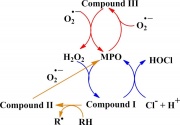

| 10:49, 19 בנובמבר 2017 | Myeloperoxidase4.jpg (קובץ) |  |

32 קילו־בייטים | Motyk | 1 | |

| 10:49, 19 בנובמבר 2017 | Myeloperoxidase3.jpg (קובץ) |  |

101 קילו־בייטים | Motyk | 1 | |

| 10:48, 19 בנובמבר 2017 | Myeloperoxidase2.jpg (קובץ) |  |

50 קילו־בייטים | Motyk | 1 | |

| 10:48, 19 בנובמבר 2017 | Myeloperoxidase1.jpg (קובץ) |  |

79 קילו־בייטים | Motyk | 1 | |